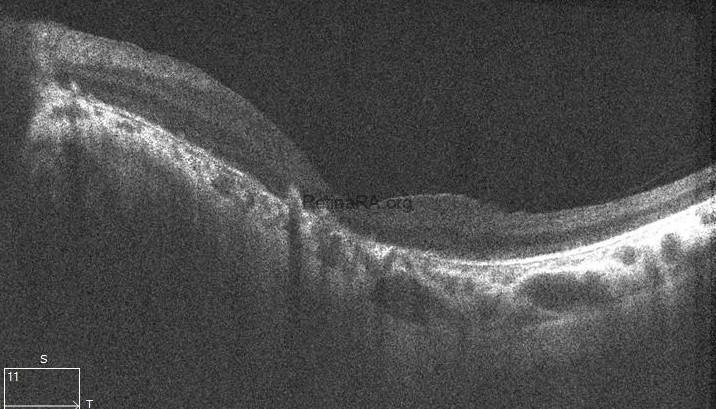

The scan of the right eye shows marked thinning of the outer retinal layers, particularly involving the outer nuclear layer and ellipsoid zone. The foveal contour is preserved; however, there is significant disruption and attenuation of the IS/OS junction and RPE band, consistent with advanced rod-cone dystrophy. In the left eye, generalized outer retinal atrophy is seen with loss of the photoreceptor integrity line and irregularity in the RPE layer. The foveal depression is shallow, and parafoveal architecture is disorganized, indicating chronic degenerative changes.

Multimodal imaging in Bardet-Biedl syndrome reveals characteristic features of retinal degeneration. Fundus photography typically shows attenuated vessels, waxy optic disc pallor, and bone spicule pigmentation in the mid-periphery. Fundus autofluorescence often demonstrates patchy areas of hypoautofluorescence correlating with RPE loss. OCT reveals outer retinal thinning, disruption of the ellipsoid zone, and foveal architecture loss in later stages. Electroretinography shows diminished or extinguished scotopic and photopic responses, confirming widespread rod-cone dysfunction.